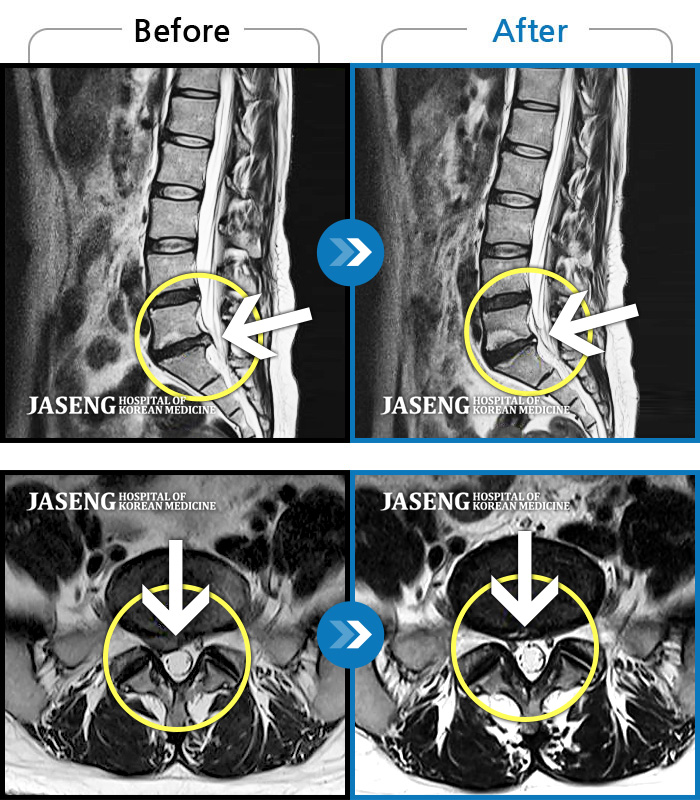

Before

After

허리 통증과 우측 허벅지 통증 및 저림 증상 지속되어 내원하셨습니다.

2022.08.20 ~ 2024.11.08